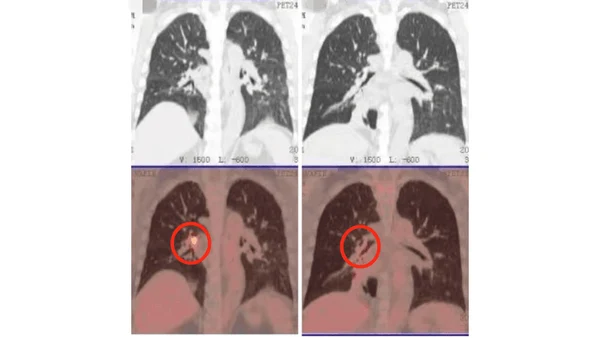

• Через 2 месяца: Опухоль в легком практически исчезла, метастазы в лимфоузлах значительно уменьшились. • Сердечная функция стабилизировалась - лечение не усугубило риски. • Возврат к активной жизни: Рамли общается с пациентами из других стран, используя переводчик, и вдохновляет их своим примером.

КТ-снимки подтвердили: динамика положительная, болезнь отступает

26 февраля 2024 года результаты КТ показали, что опухоль легкого значительно уменьшилась